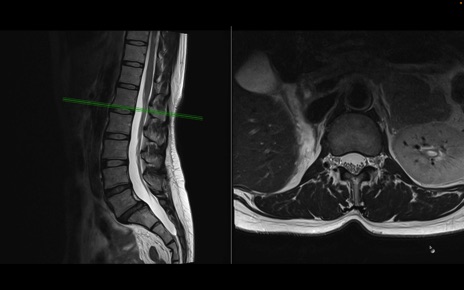

腰椎MRI

T1WI(矢状断像)

T2WI(矢状断像)